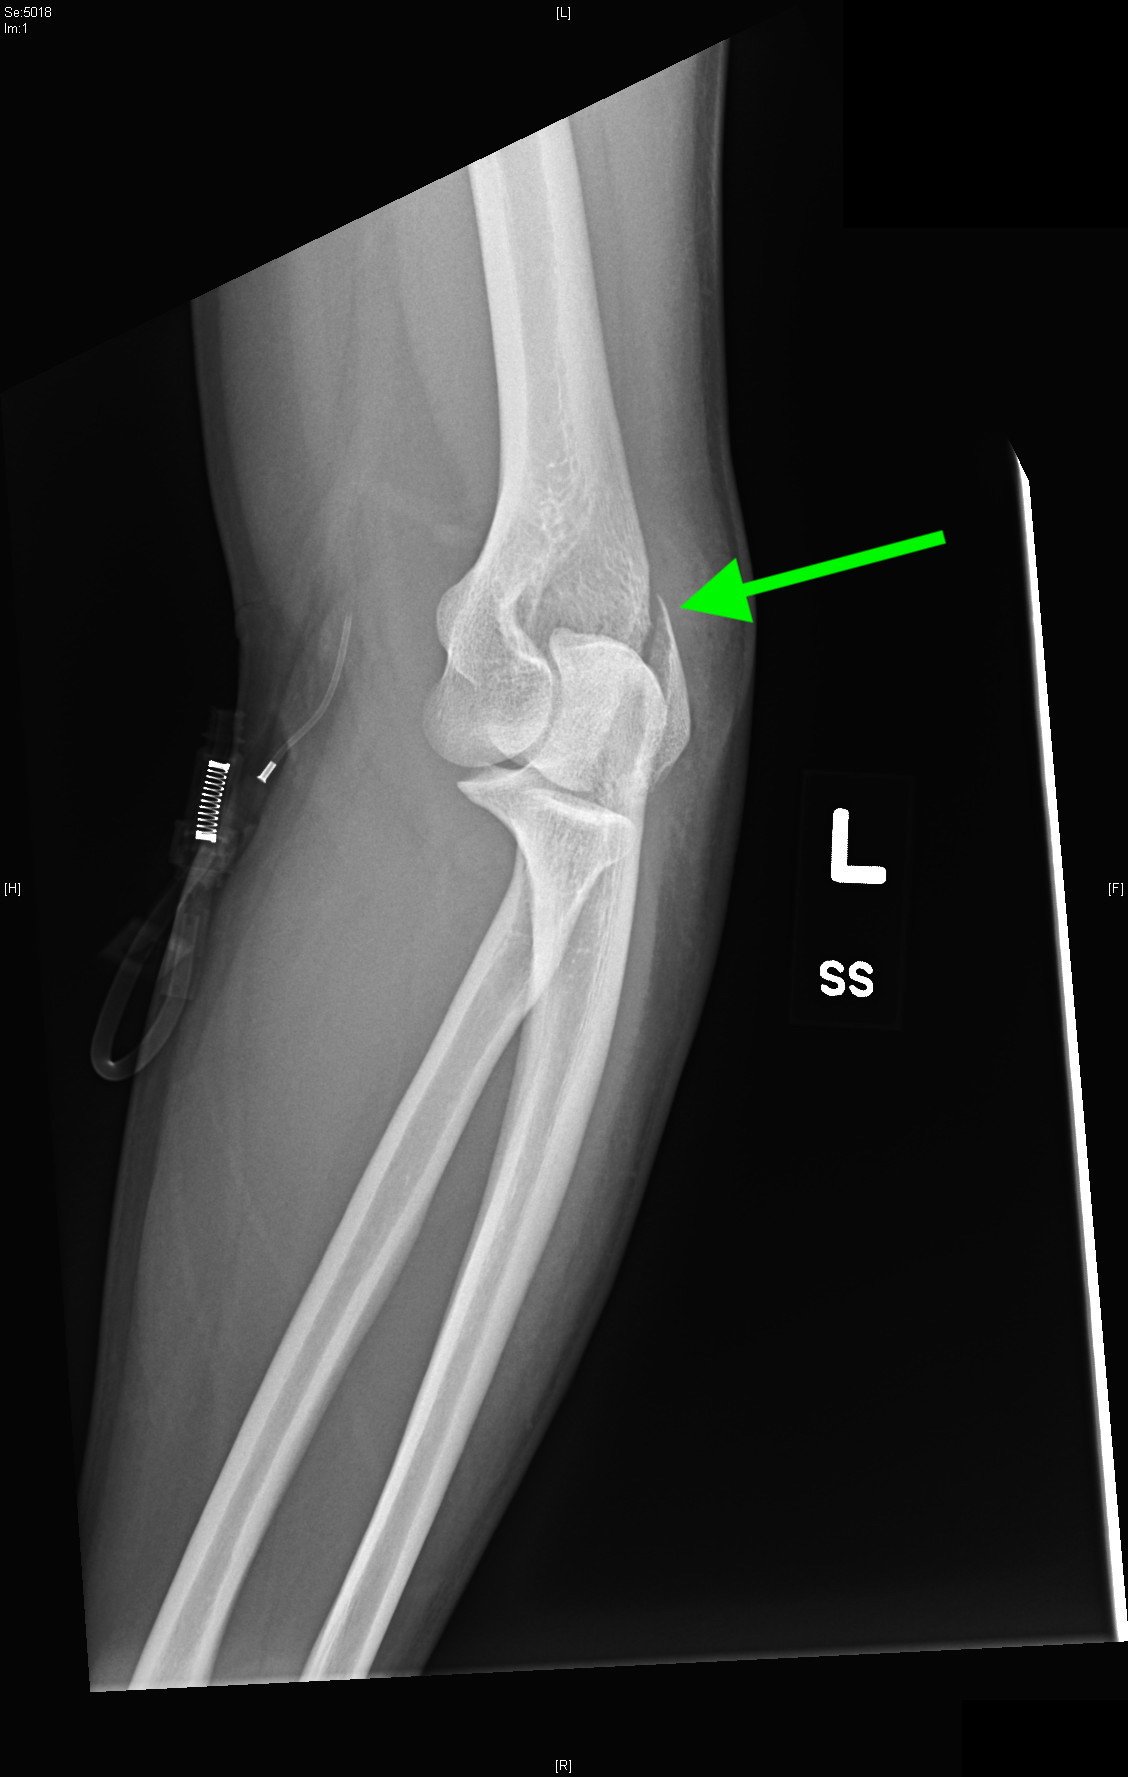

Lateral Epicondyle Fracture

Radiographs of the right elbow revealed an acute fracture through the lateral epicondyle with dislocation of the radial head inferiorly. Radiographs of the left elbow revealed a slightly angulated fracture through the lateral epicondyle.